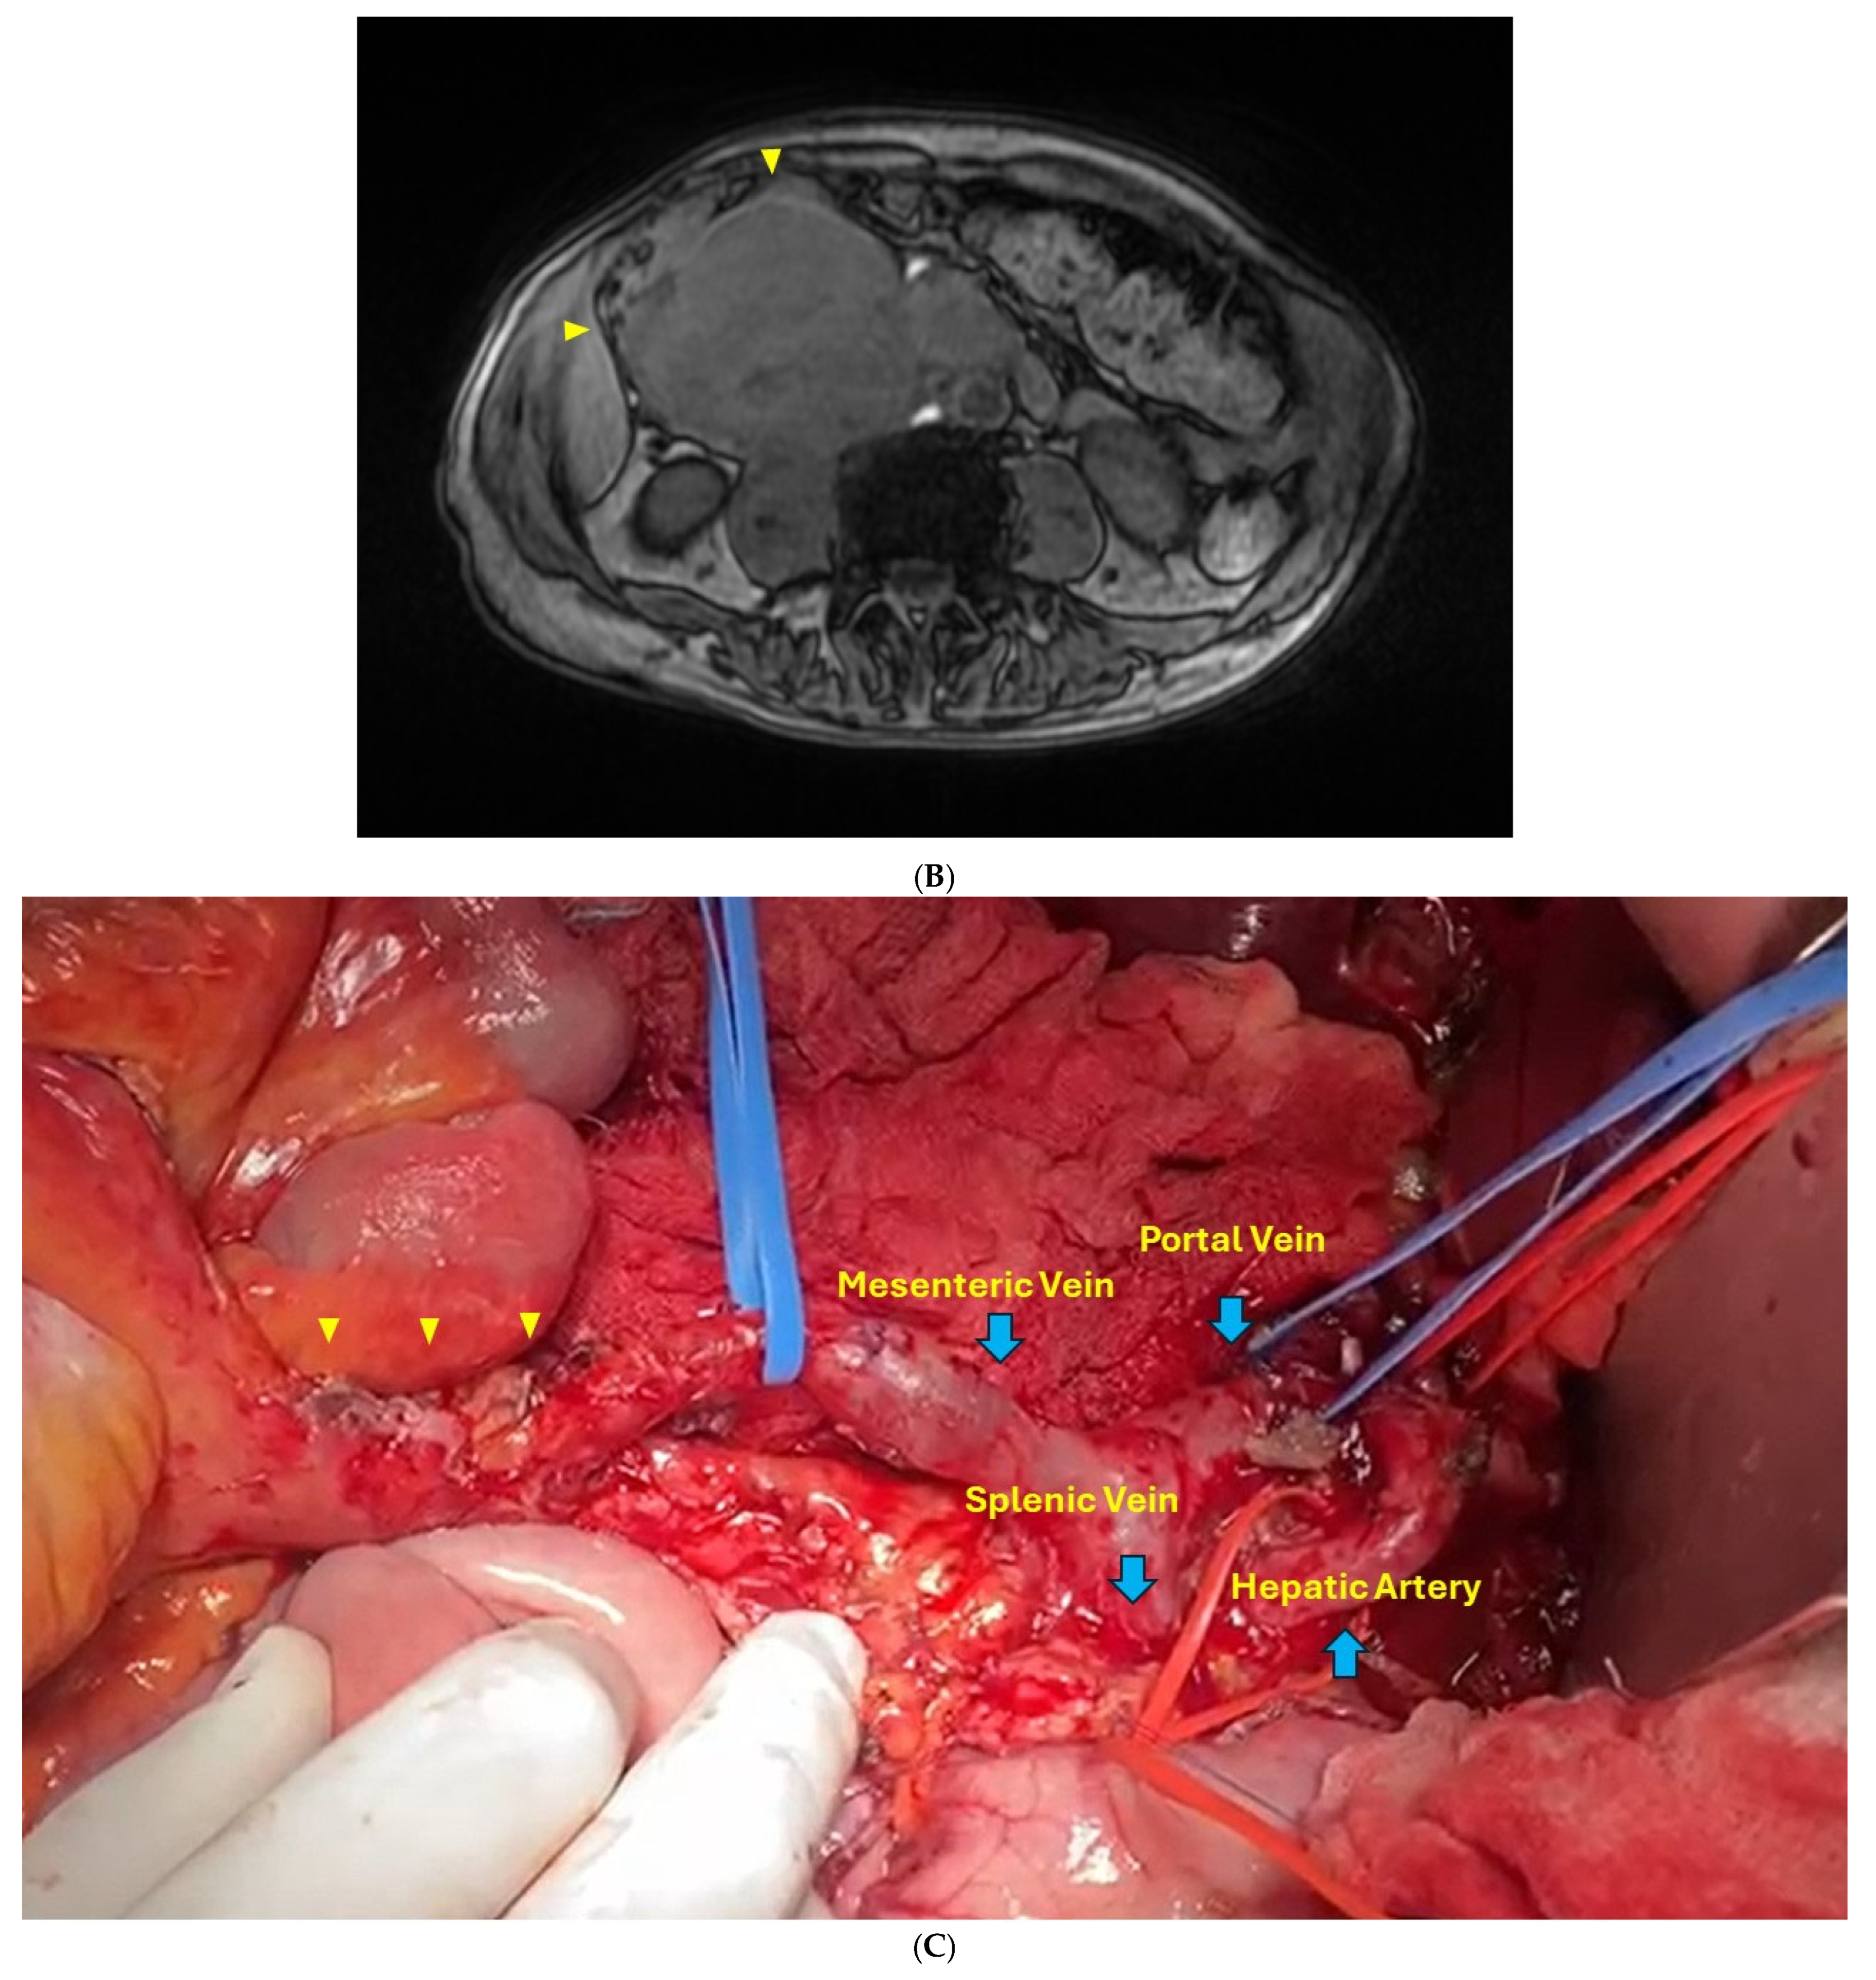

2.1. Case Report 1